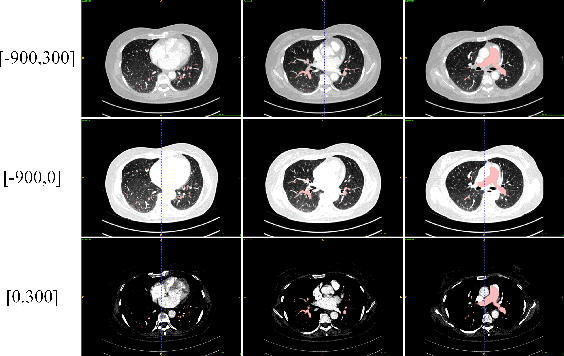

This is the technical report of the 9th place in the final result of PARSE2022 Challenge. We solve the segmentation problem of the pulmonary artery by using a two-stage method based on a 3D CNN network. The coarse model is used to locate the ROI, and the fine model is used to refine the segmentation result. In addition, in order to improve the segmentation performance, we adopt multi-view and multi-window level method, at the same time we employ a fine-tune strategy to mitigate the impact of inconsistent labeling.